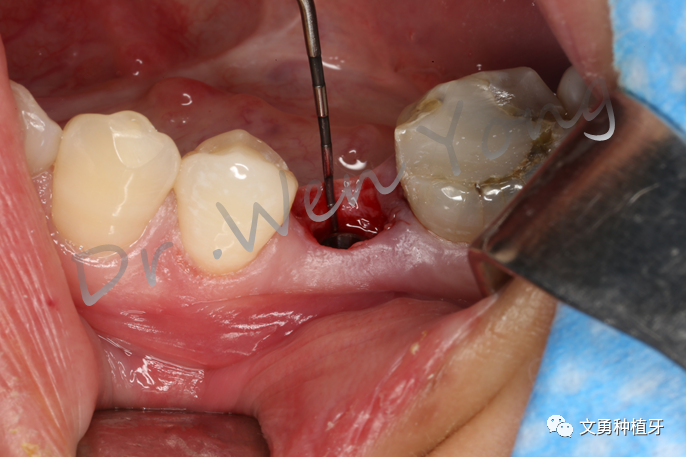

①微创拔除75,搔刮牙槽窝

②植入士卓曼亲水BLT种植体4.1mm*12mm1枚

③初期稳定性35N·cm

④种植体位于龈下3-4mm

⑤放置临时基台

⑥3M流体树脂制作个性化愈合基台,用于维持穿龈轮廓形态